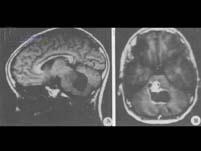

问题 脑干肿瘤最多见的是()

选项 A.胶质瘤 B.海绵状血管瘤 C.血管母细胞瘤 D.血管网状细胞瘤 E.以上都不对

答案 A